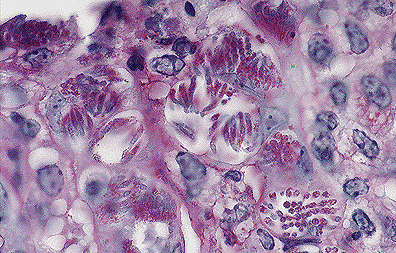

Necrotizing colitis with intraepithelial coccidial schizonts in a calf. (40X, HE, 110K)

Contributor's Diagnosis and Comments: Colitis, fibrinopurulent, diffuse, severe, with intra-epithelial coccidia.

Microscopic lesions vary in appearance among the histological slides. In the section of colon examined, clumps of fibrin containing cellular debris and inflammatory cells are adhered to the mucosa. Most crypt epithelial cells contain schizonts, gamonts, or developing oocysts. Many intestinal crypts are distorted or have been destroyed as a result of coccidial infection. Erosion and ulceration of the mucosa have occurred. A lymphoplasmacytic inflammatory reaction is present in the lamina propria.

The most likely etiologic agent is Eimeria zuernii which is one of the most common and pathogenic coccidia of ruminants. The other is E. bovis. Life cycles of both agents are similar. Large schizonts typical of either E. bovis or E. zuernii were not observed in multiple sections of jejunum and ileum examined. Eimeria bovis infects endothelial cells in lacteals of the jejunum located several meters anterior to the ileocecal valve; whereas, E. zuernii schizonts are found in the lamina propria of the terminal ileum. Secondary schizonts and gamonts of E. zuernii develop in the glands of the cecum and colon but not terminal ileum.

AFIP Diagnosis: Colon: Colitis, necrotizing, subacute, diffuse, moderate, with erosions, and myriad intracellular coccidia, Hereford-cross, bovine, etiology consistent with Eimeria sp.